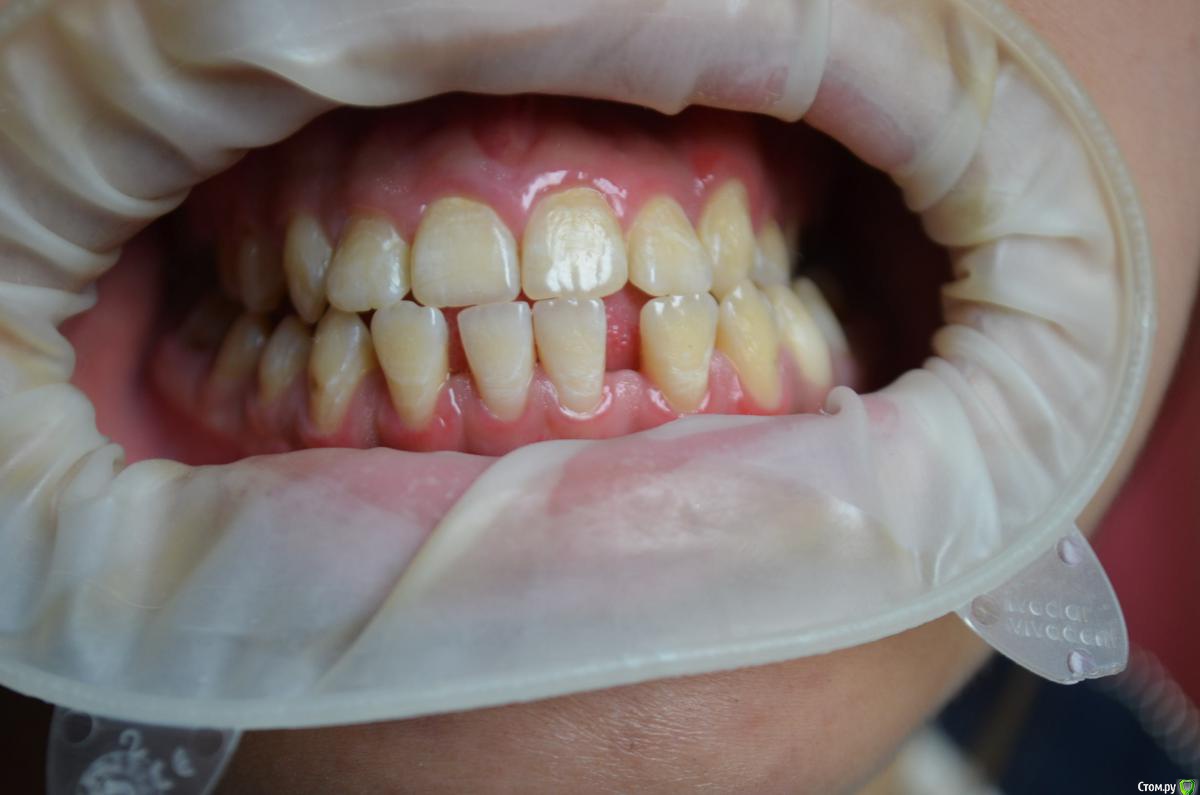

Пациентке 16 лет носила брекеты 4 года (переносила), нижний фронт зубов подвижен, слизистая воспалена, тремы на н.ч, множественный кариес под брекетами после снятия, сейчас на этапе эндолечения. Помогите советами как правильно и с чего начать , на в.ч. поставил ретейнер, на нижней пока идет терапевтическое лечение. ТРГ нету